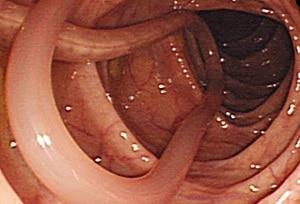

Consulta de Desparasitação Intestinal

Na consulta de desparasitação intestinal, é realizada uma avaliação detalhada do estado do seu organismo, com foco na identificação de possíveis parasitas, bactérias, fungos e vírus que possam estar comprometendo o equilíbrio intestinal.

Para isso, recorremos a um exame de bioressonância quântica, um método não invasivo que analisa as frequências energéticas do corpo e permite identificar desequilíbrios relacionados a microrganismos nocivos. Sempre que necessário, podem ser solicitadas análises laboratoriais complementares para confirmação.

O exame por bioressonância capta as frequências celulares e identifica padrões alterados que indicam a presença de parasitas ou outros agentes nocivos.

Presença visível de vermes nas fezes em alguns casos.